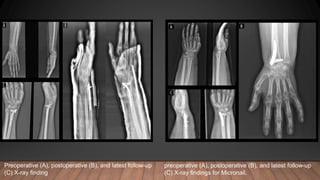

preoperative (A), postoperative (B), and latest follow-up

(C) X-ray findings for Micronail.

(C) X-ray finding